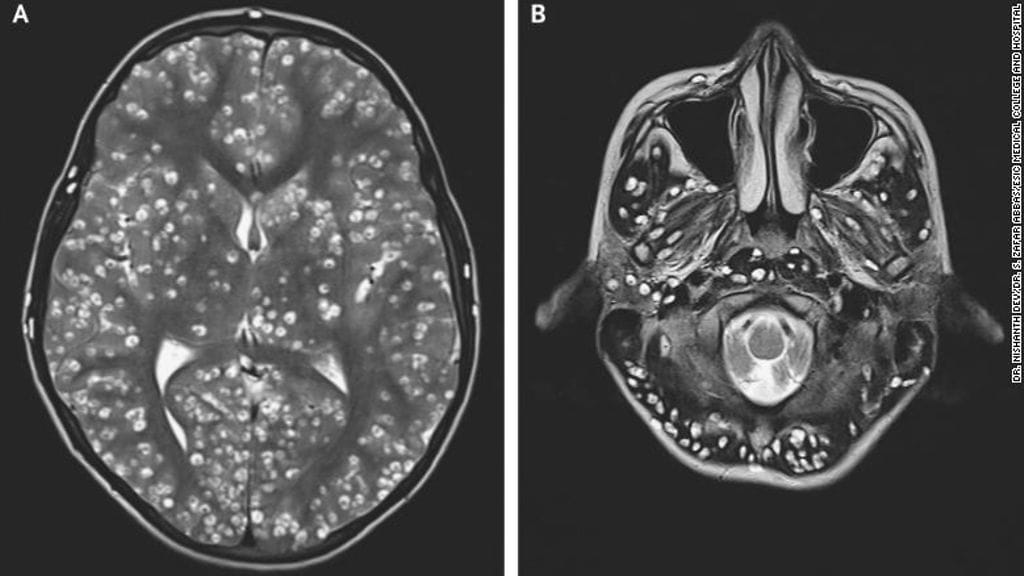

Magneettikuvauksissa lääkärit löysivät pojan aivoista useita kystia, eli nesteen täyttämiä rakkuloita. Vahinkoja oli aivokuoressa sekä aivorungossa, jossa myös pikkuaivot sijaitsevat.

Lääkärit löysivät kystia myös pojan oikeasta silmästä sekä oikeasta kiveksestä. Kystien määrän ja sijainnin vuoksi he eivät voineet hoitaa potilasta varsinaisilla matolääkkeillä, jotka olisivat voineet aiheuttaa verenvuotoa ja tulehduksen aivoissa.